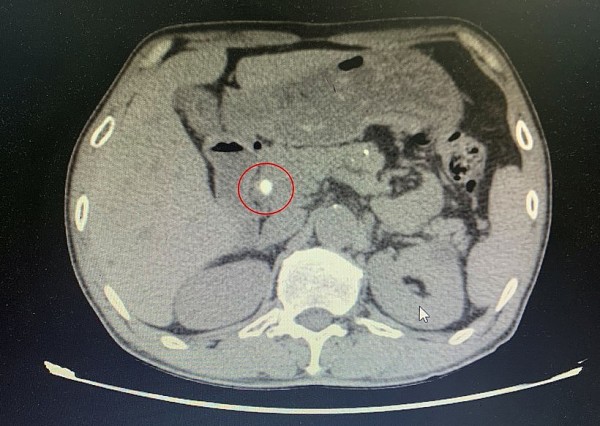

Phẫu thuật nội soi lấy dị vật kim loại trong gan – Ca bệnh hiếm gặp được xử trí thành công